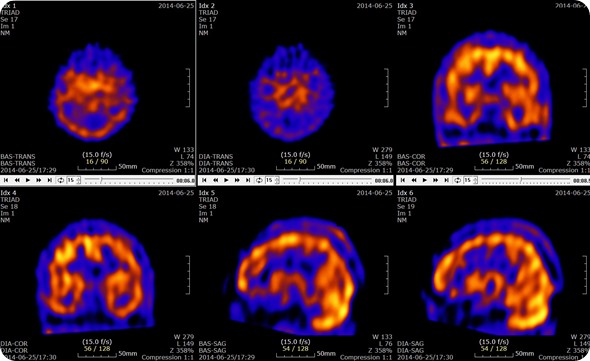

Brain SPECT with Acetazolamide Slices. Credit: U2em, shared under licenses Creative Commons Attribution-Share Alike 3.0 Unported

These rays are then detected by the gamma camera which rotates through 360 degrees around the patient. This rotation around the patient enables the cross-sectional images to be assembled three-dimensionally as in computed tomography. This means that the resulting images are able to be viewed either as a three dimensional entity or as a series of thin slices through the subject.

SPECT scans are used to determine which parts of the brain are affected by various disorders including Dementia, Epilepsy and head injuries. These are characterized by too much activity in a particular area, too little activity in particular areas or asymmetrical activity across the brain where the activity should be symmetrical. These are all determined through the comparison of the scan results to the standard normal brain scans.